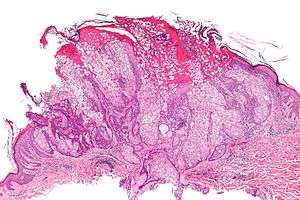

| Micrograph of a sebaceous adenoma. H&E stain. | |

A sebaceous adenoma, a type of adenoma, a cutaneous condition characterized by a slow-growing tumor usually presenting as a pink, flesh-coloured, or yellow papule or nodule.[1]:662[2]